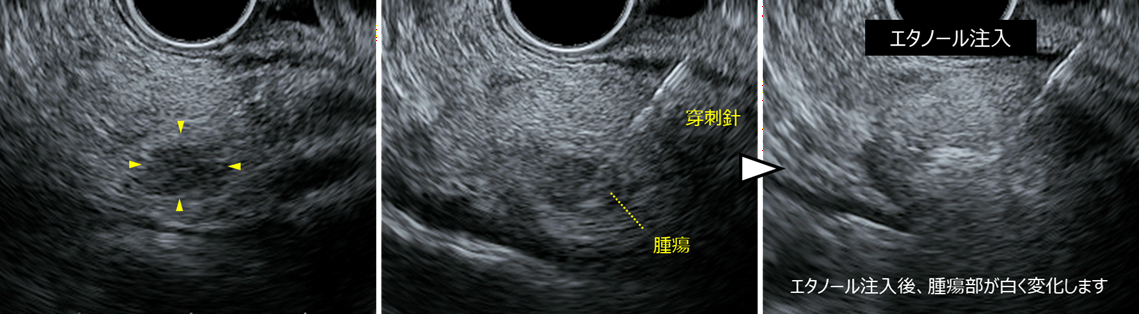

膵頭部に約8 mmの腫瘍を認め、EUS-FNAを施行しました。病理診断の結果、悪性度の低い NET G1 と診断されました。腫瘍径が小さく悪性度も低いことから、超音波内視鏡下エタノール注入療法を行いました。

左:境界明瞭な8mm大の低エコー腫瘤を認めます。

中:FNA針で腫瘍を穿刺します。

右:腫瘍の大きさに合わせてエタノールを注入します。注入後はこのように腫瘍内部が白く変化し、薬剤が腫瘍内に広がったことが確認できます。

超音波内視鏡(Endoscopic Ultrasound:EUS)では、膵頭部に境界明瞭な約8 mmの低エコー腫瘤を認めました。穿刺針で腫瘍を穿刺し、腫瘍内にエタノールを注入しました。エタノール注入後、腫瘍は白く変化し、薬剤が腫瘍内に行き渡ったことが確認されました。